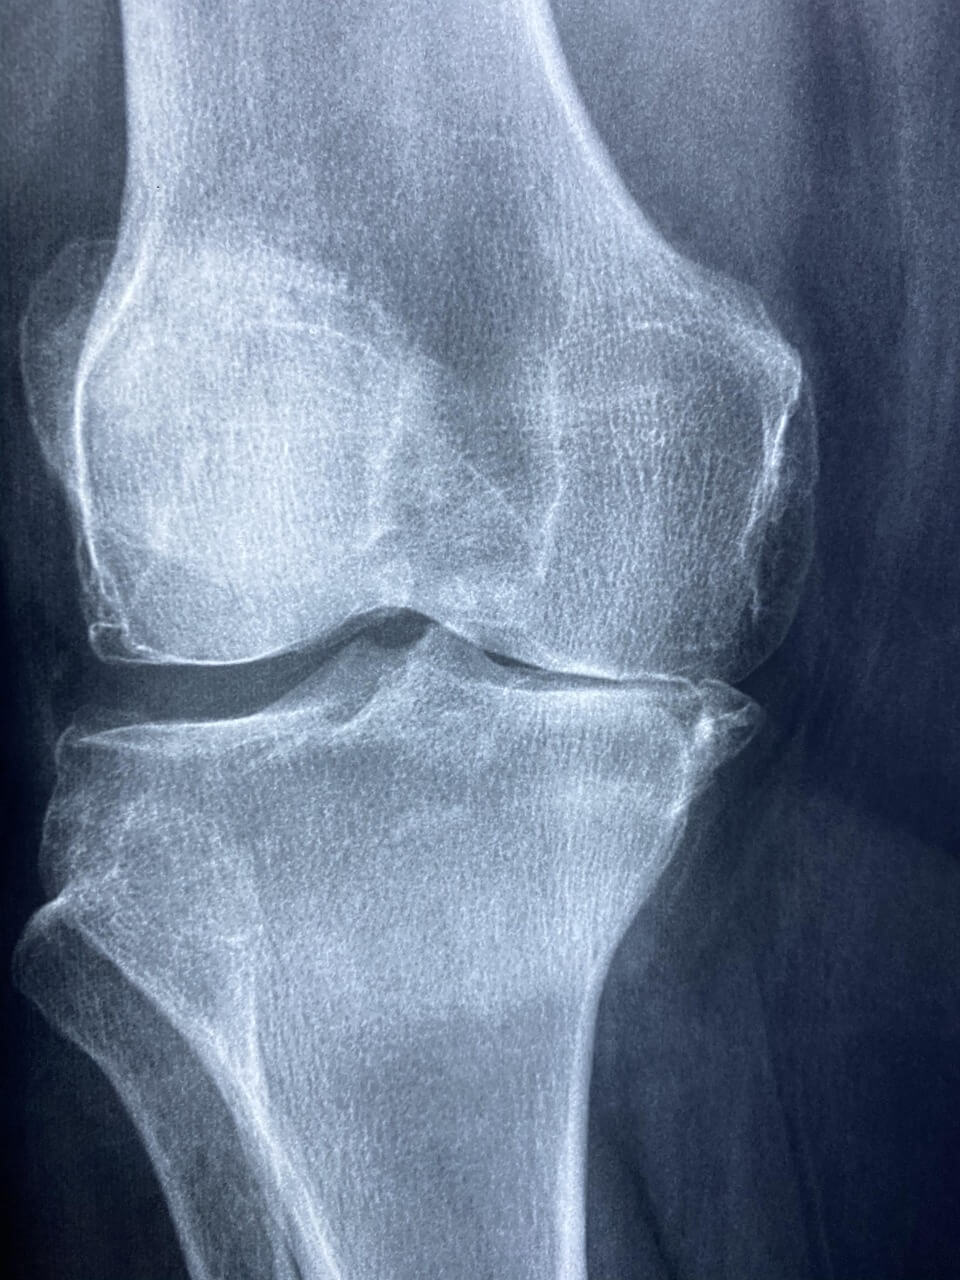

- 진단 기준: 정형외과 전문의의 인공관절 수술 필요 소견